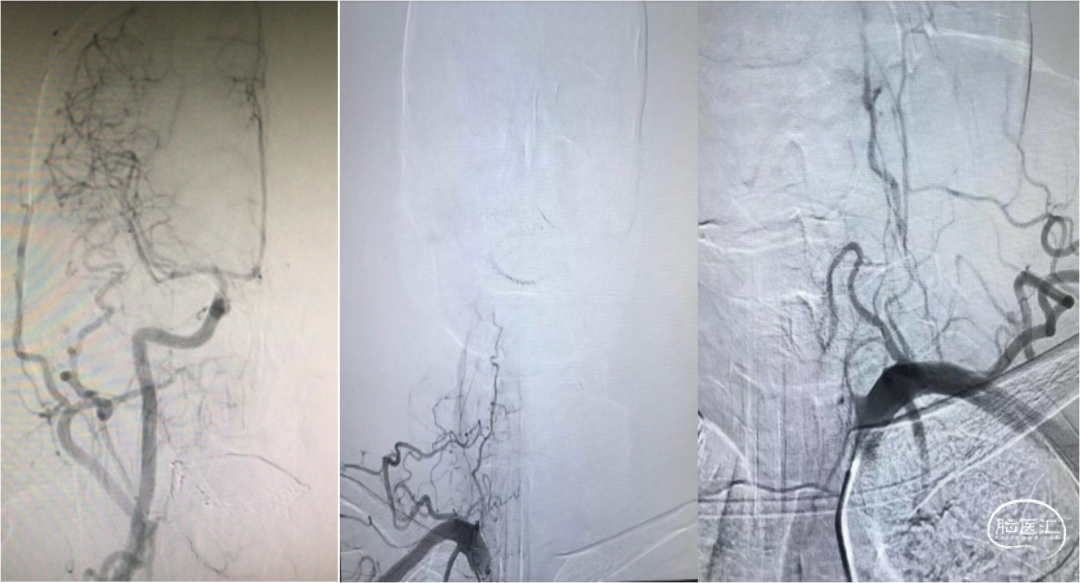

造影提示右侧椎动脉闭塞,未见显影,左侧椎动脉起始部显影不佳。观察后左侧椎动脉V1段显影不畅,考虑起始部狭窄可能,串联病变。用泥鳅导丝尝试通过左侧椎动脉起始部,导丝进入真腔。更换Stiff导丝,交换Neuromax长鞘至左侧椎动脉V1段。即刻长鞘中抽吸,可见血栓抽出。

长鞘路图造影,发现椎动脉远端不显影,局部大量血栓。路图下将普微森PASSAGEWAY™中间导管送至血栓近端,连接负压泵抽吸,缓慢回撤导管,可见导管头端被吸住的血栓。